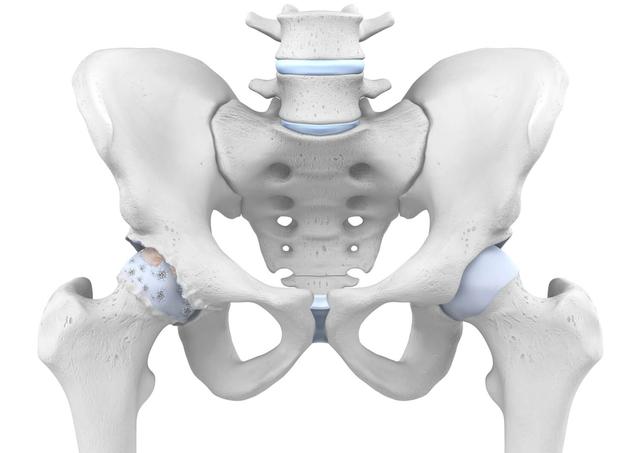

– Coxarthrose ist eine Form der Arthrose, die durch Verschleiß bedingte Knorpelschäden im Hüftgelenk verursacht werden.

– Bei einer Coxarthrose ist der Knorpel von Hüftkopf und/oder Hüftpfanne beschädigt, was zu Schmerzen im Hüft- und Leistenbereich führt.

Die Coxarthrose, auch bekannt als Hüftarthrose, ist eine häufig auftretende Form der Arthrose. Sie tritt vor allem bei älteren Menschen ab 50 Jahren auf. Bei dieser Erkrankung kommt es zu Verschleißerscheinungen und Schäden am Knorpel des Hüftgelenks. Dadurch entstehen Schmerzen im Hüft- und Leistenbereich sowie eine starke Einschränkung der Beweglichkeit.

Der Knorpelschaden an der Hüfte führt dazu, dass der Druck auf den darunter liegenden Knochen erhöht wird. Der Knorpel wird immer dünner, reißt teilweise ein und raut auf. Dadurch verengt sich der Gelenkspalt immer mehr und es kann sogar zur vollständigen Abnutzung des Knorpels kommen.

Coxarthrose, auch bekannt als Hüftarthrose, bezeichnet den Verschleiß des Knorpels im Hüftgelenk. Es handelt sich um eine häufige Form der Arthrose, die vor allem bei älteren Menschen ab 50 Jahren auftritt. Durch den Knorpelabbau kommt es zu Schmerzen im Hüft- und Leistenbereich sowie zu einer Einschränkung der Beweglichkeit.

Der Knorpelschaden bei einer Coxarthrose führt dazu, dass der Knorpel dünner wird, einreißt und rau wird. Dadurch erhöht sich der Druck auf den darunter liegenden Knochen. Der Gelenkspalt verengt sich immer mehr und in manchen Fällen kann der Knorpel vollständig abgerieben werden. Dies führt dazu, dass die Knochen ohne Schutz aufeinander reiben.

Coxarthrose, auch bekannt als Hüftarthrose, ist eine Form der Arthrose, bei der es zu Verschleiß und Schädigung des Knorpels im Hüftgelenk kommt. Diese Erkrankung tritt häufig auf und betrifft in erster Linie ältere Menschen ab 50 Jahren. Der Knorpelüberzug von Hüftkopf und/oder Hüftpfanne ist bei Coxarthrose beschädigt, was zu Schmerzen im Bereich der Hüfte und Leiste führt. Die Beweglichkeit des Gelenks ist stark eingeschränkt.